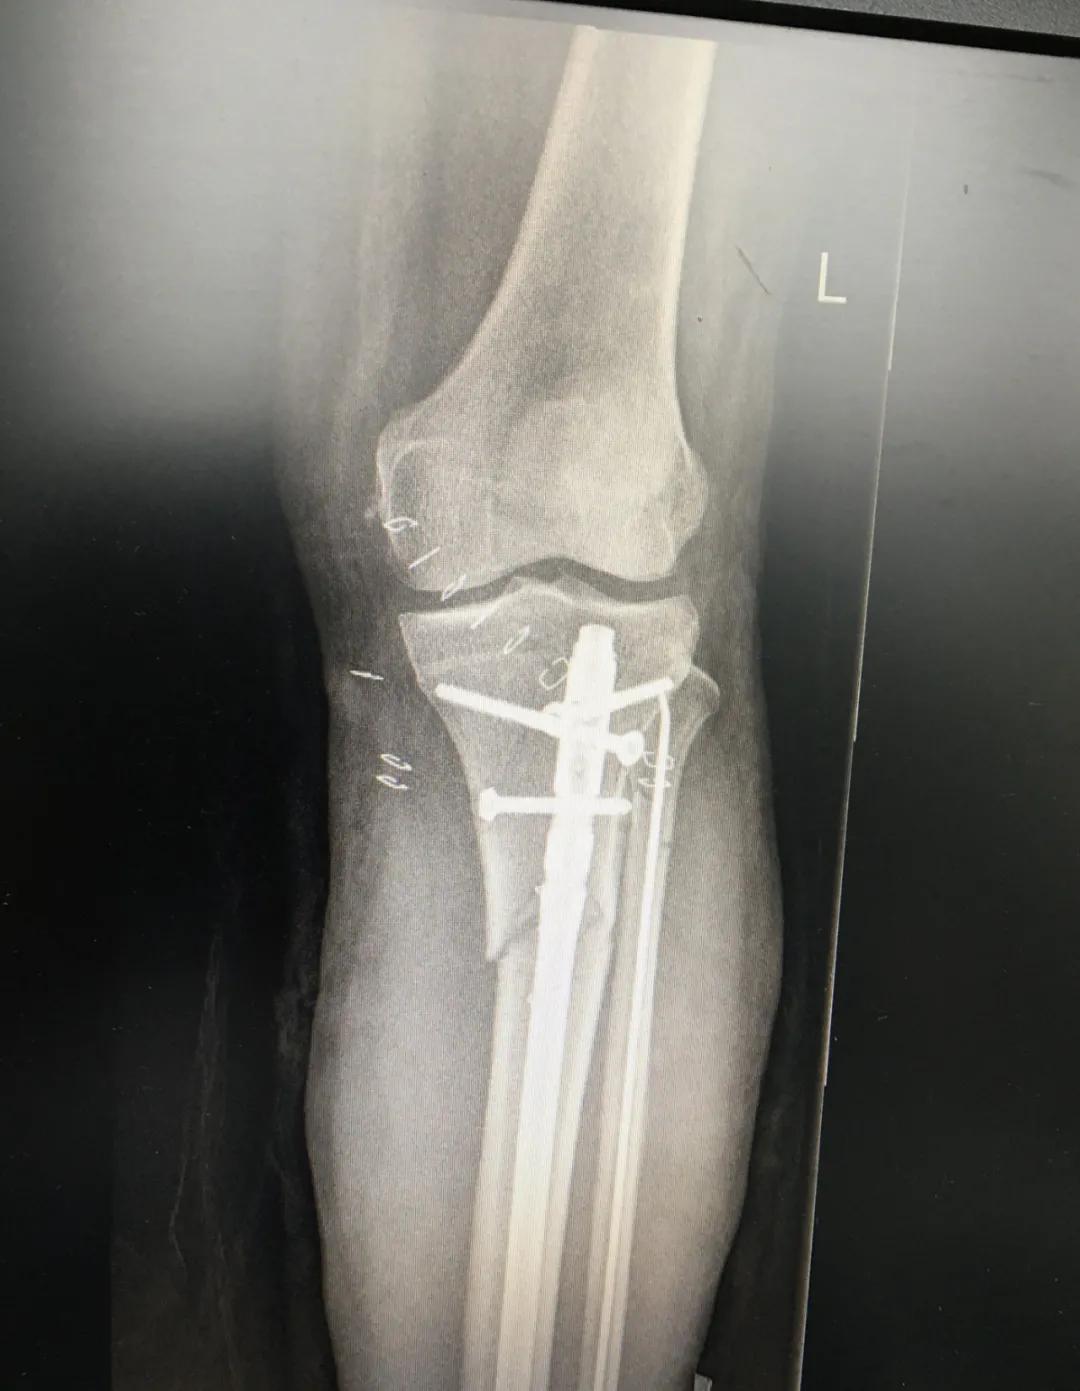

为患者实施的骨折微创复位固定技术是创伤骨科的特色技术。相较传统手术需要20公分的切口,微创手术只需要3公分左右。闭合复位髓内钉固定技术、经皮插板内固定技术(mippo技术)、闭合复位空心螺钉固定技术等一系列的微创复位固定技术,具有切口小、出血少、创伤小、愈合快、疤痕小等优点,骨折术后并发症明显降低,患者还可以早期负重功能锻炼。

周先生说:“早晨7点多,屈主任就来到我们床前会诊。赵主任临床经验丰富,这次我妻子做的骨折微创手术很成功,管床的陆医生虽然年轻但是非常有耐心,对于这样的结果,我们非常欣喜!”

另一位患者朱先生因车祸导致了右胫腓骨骨折,同样的小腿三段骨折,实施了微创闭合复位髓内钉固定术后,目前已经逐步进行康复功能锻炼。